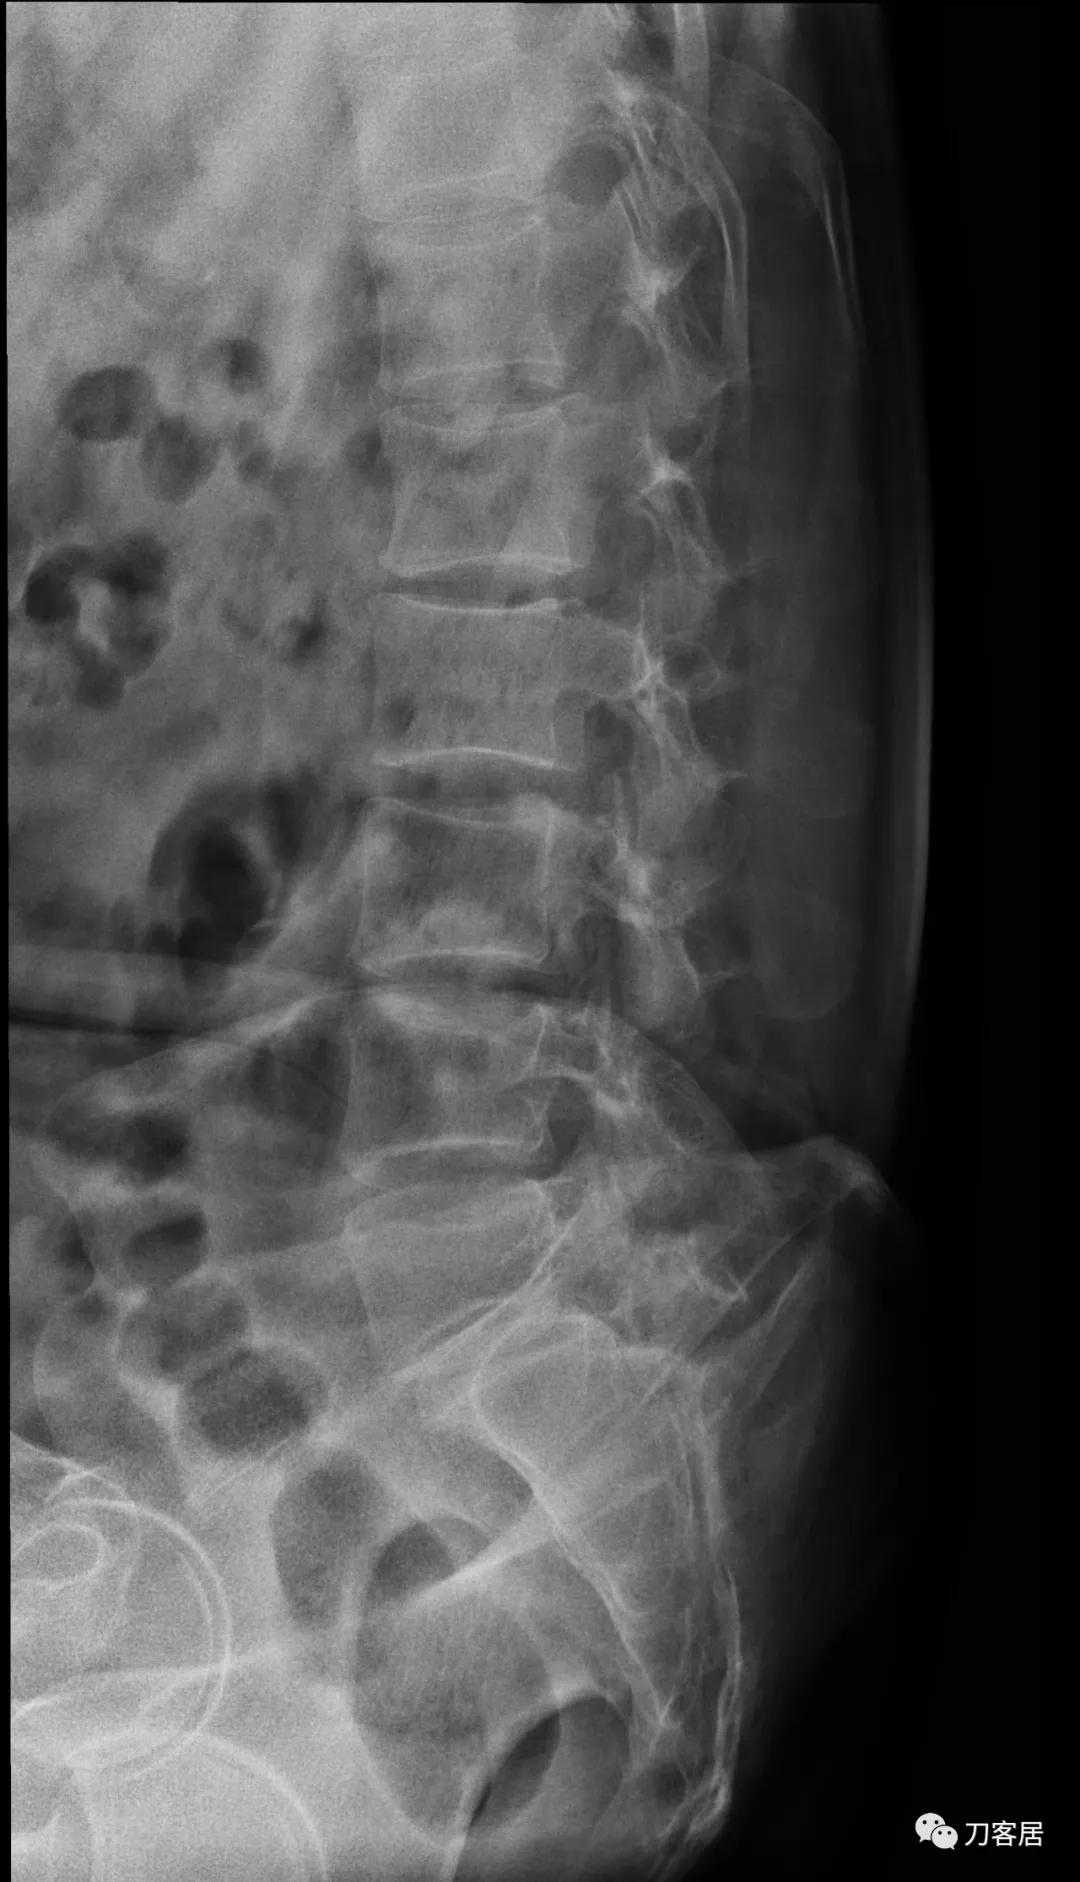

自带影像学检查提示腰5椎体前滑脱,腰5峡部裂,椎管狭窄不严重。

诊断:腰5峡部裂,腰5椎体前滑脱1度,骨质疏松症。

图6. 20210616术前腰椎过屈位X线片